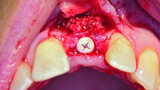

Fig. 4: The implant site was uncovered after five months.